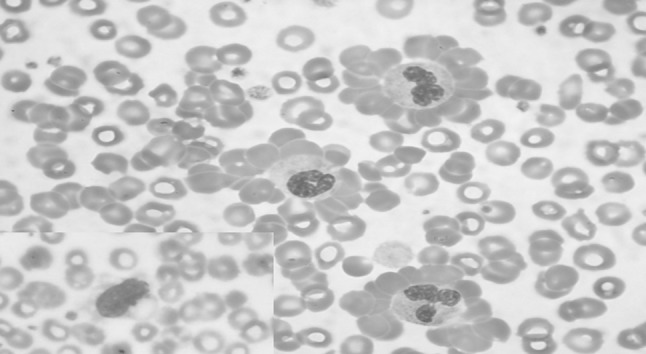

A 43 year old male presented with complaints of episodes of jaundice, mild fever and generalized body ache of 20 days duration. He also complained of episodic passage of reddish colour urine since 20 days. The patient had a past history of similar complaints 5 years back, when he was diagnosed to have AIHA and was treated with prednisolone at a dose of 35 mg/day, which was gradually tapered off. Examination revealed pallor and icterus with mild hepatosplenomegaly. Investigations showed haemoglobin of 9.9 gm/dl, corrected reticulocyte count of 5.8 %, serum total and conjugated bilirubin of 2.6 and 1.0 mg/dl respectively. Plasma haemoglobin and serum lactate dehydrogenase were elevated measuring 62.8 mg/L and 1296 U/L, respectively. Urine routine examination was positive for protein, bilirubin and blood/haemoglobin (2+), while microscopic examination showed only 2–3 RBC’s per high power field. Peripheral blood smear showed frequent RBC rosettes around neutrophils (Fig. 1). All the rosettes were typically seen with neutrophils and none around monocytes (inset Fig. 1). Direct antiglobulin test was strongly positive for IgG and C3d complement (4+). The patient was re-initiated on prednisolone at a dose of 35 mg/day.

Fig. 1.

May Grunwald Giemsa stained peripheral blood smear showing presence of numerous neutrophil erythrocyte rosettes (×400) and inset showing presence of a monocyte without RBC rosetting